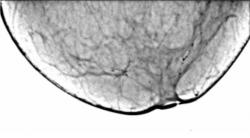

Протокол рентгенологического исследования (кратко). На снимке в прямой проекции (1) общая скиалогическая картина инволютивной молочной железы, с хорошо прослеживающимися на фоне жировой ткани соединительнотканными компонентами стромы, отдельными очаговыми уплотнениями паренхимы железы. В верхнем наружном квадранте прослеживается цепочка макрокальцинатов различной величины и формы, по расположению, напоминающая ход млечного протока, что хорошо видно также на снимке в боковой проекции (2). В верхнем внутреннем квадранте железы, а также ретроареолярно в передних отделах молочной железы определяются отдельные макрокальцинаты. На боковом снимке (2), кальцинаты, локализующиеся в верхнем медиальном квадранте группируются с образованием цепочки. «Навигатором» выделена цепочка кальцинатов, локализующаяся в верхнем наружном квадранте. При цифровой обработке в условиях «фактор» вокруг кальцинатов появляется, так называемый, «поясок безопасности».

2. Снимок в боковой проекции